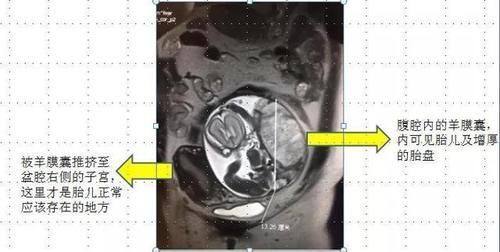

这名产妇怀孕26周,但是胎儿却不在子宫里,而是在产妇的直肠附近生长。

而且胎盘的血管密密麻麻的在直肠内疯长,把产妇腹内其他组织器官压迫到了边缘。

整个腹腔内的器官组织都因为长时间遭受压迫而变形移位,医生们都倒吸凉气。

而且,孕期25周,但胎儿实际发育只有22周,明显是生长受限,而且胎盘已经坏死了三分之一。

原发性腹腔妊娠比较罕见,临床多为继发性腹腔妊娠,王女士情况很特殊,早期是宫外孕,孕囊卡在输卵管内,后流产从输卵管内挤出,滑落到腹腔内。胎儿能长到这么大月份,实在是个奇迹!